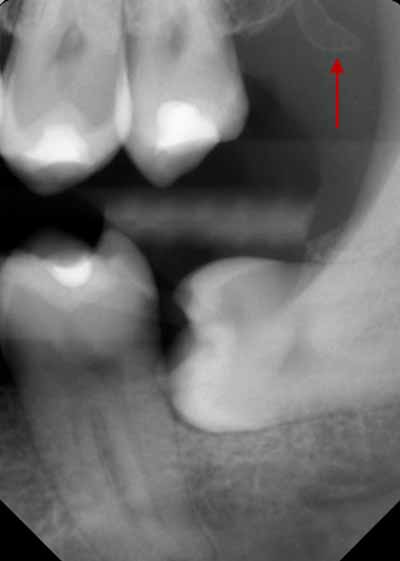

歯の発育がまだ完了していない子供や青少年では、歯列の発育段階に応じて歯の外観が変化すると考えられます。歯根の発達が不完全な歯は根尖性歯周炎に似ている可能性があるため、レントゲン写真で根尖周囲の変化を確認する際には、この点に留意することが重要です (画像4を参照)。